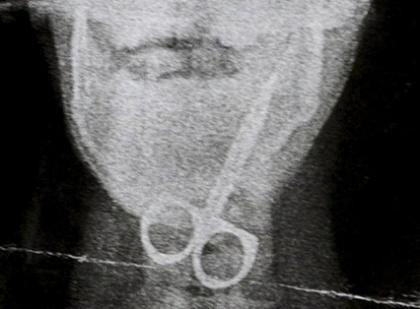

Άγιο είχε 12χρονος από την Βρετανία, ο οποίος κατάπιε το ψαλιδάκι για τα νύχια και τη γλύτωσε με μόνο ελάχιστες γρατζουνιές.

Ο μικρός Curtis Frances είναι παιδί με μαθησιακές δυσκολίες πράγμα που τον κάνει να μην έχει αίσθηση του κινδύνου. Έτσι, όταν η μητέρα του Karen πήγε για λίγα λεπτά στο διπλανό δωμάτιο, ο Curtis πήρε το ψαλίδι, το τοποθέτησε στο στόμα του και το κατάπιε.